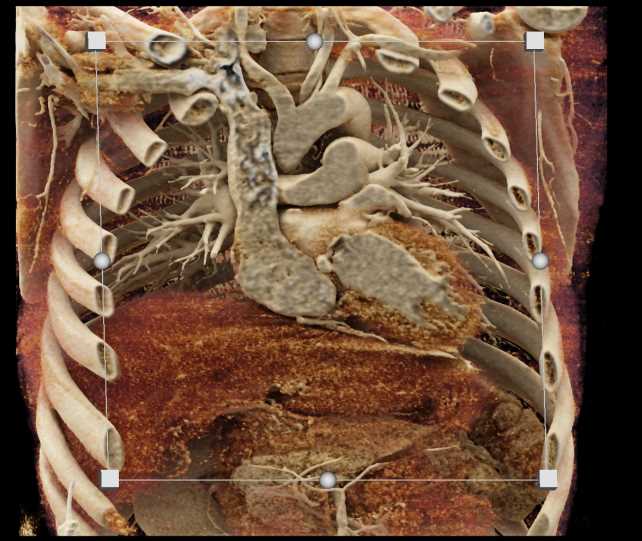

Diagnosis

Aortic Valve Repair